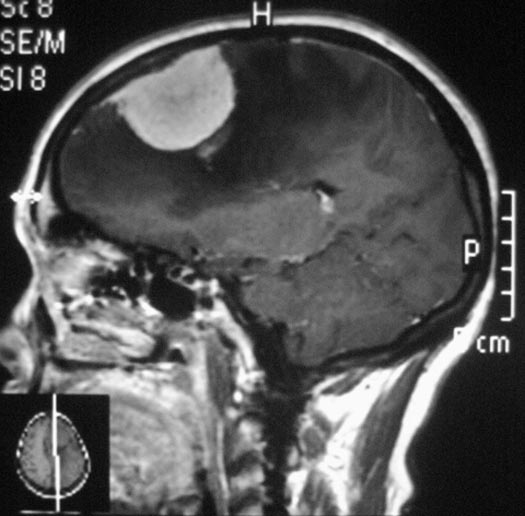

惴惴不安地去医院检查,CT结果提示:左侧额部占位,考虑脑膜瘤可能性大。广东三九脑科医院头颅MR检查提示肿瘤大小为:44.9mm×42.5mm×38.2mm。

完善相关检查后,综合神经外科的鲁明主任主刀在全麻下行左侧额部镰窦旁凸面脑膜瘤切除术,术中导航定位肿瘤体表投影,显微镜下见灰白色肿瘤组织,血供丰富,边界清楚,周围脑组织水肿软化,肿瘤未与大脑镰粘连,分离后予肿瘤全切,肿瘤边缘硬膜予以扩大切除,镜下达辛普森I级切除。手术后,林阿姨的术前症状都已消失,没有出现任何术后并发症。术后病理结果为:上皮型脑膜瘤。